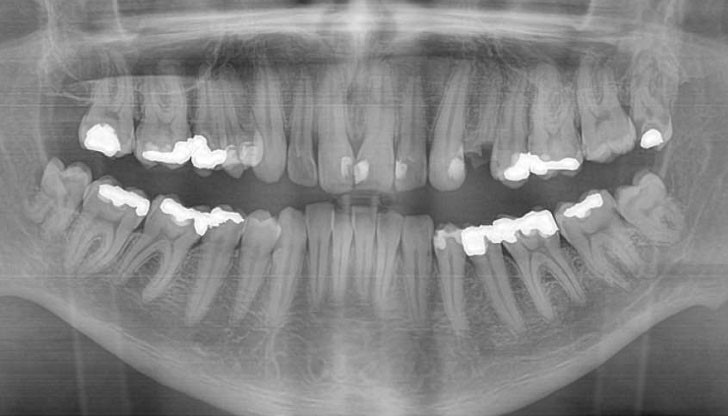

Кариесите са една от най-досадните болежки — боли те зъб, а иначе нищо друго ти няма.

В един момент обаче започва да боли много повече. Понякога обаче пломбите не могат да помогнат, защото дупката е много голяма, зъбът се руши и в крайна сметка се стига до неговото вадене… Е, това може едини ден вече да не е проблем, след като учени случайно са открили начин за естественото регенериране на зъбите, пише SMART NEWS.

В контролиран тест, учените са третирали кариесите на мишки с малки дози от лекарството, познато като tideglusib. То се използва за лечение на болестта на Алцхаймер и вече е клинично тествано. Това, което изследователите открили е, че tideglusib действа на стволовите клетки във вътрешността на зъба и така го карат да се самолекува.

Зъбите, както може би знаете, са изградени от емайл. Той обаче е само най-външната част от зъба, докато във вътрешността си той е съставен от дентин и меко ядро, в което се намират стволовите клетки. Тези стволови клетки всъщност регенерират повредения дентин, но не са достатъчно мощни, за да излекуват цял кариес.

Ето къде идва и работата на tideglusib — учените са поставили малки биоразградими гъби, просмукани с лекарството, в зъбите на мишките. С времето те се разградили и били заменени от чисто-нов синтезиран дентин, което затворило кариесите по естествен път.